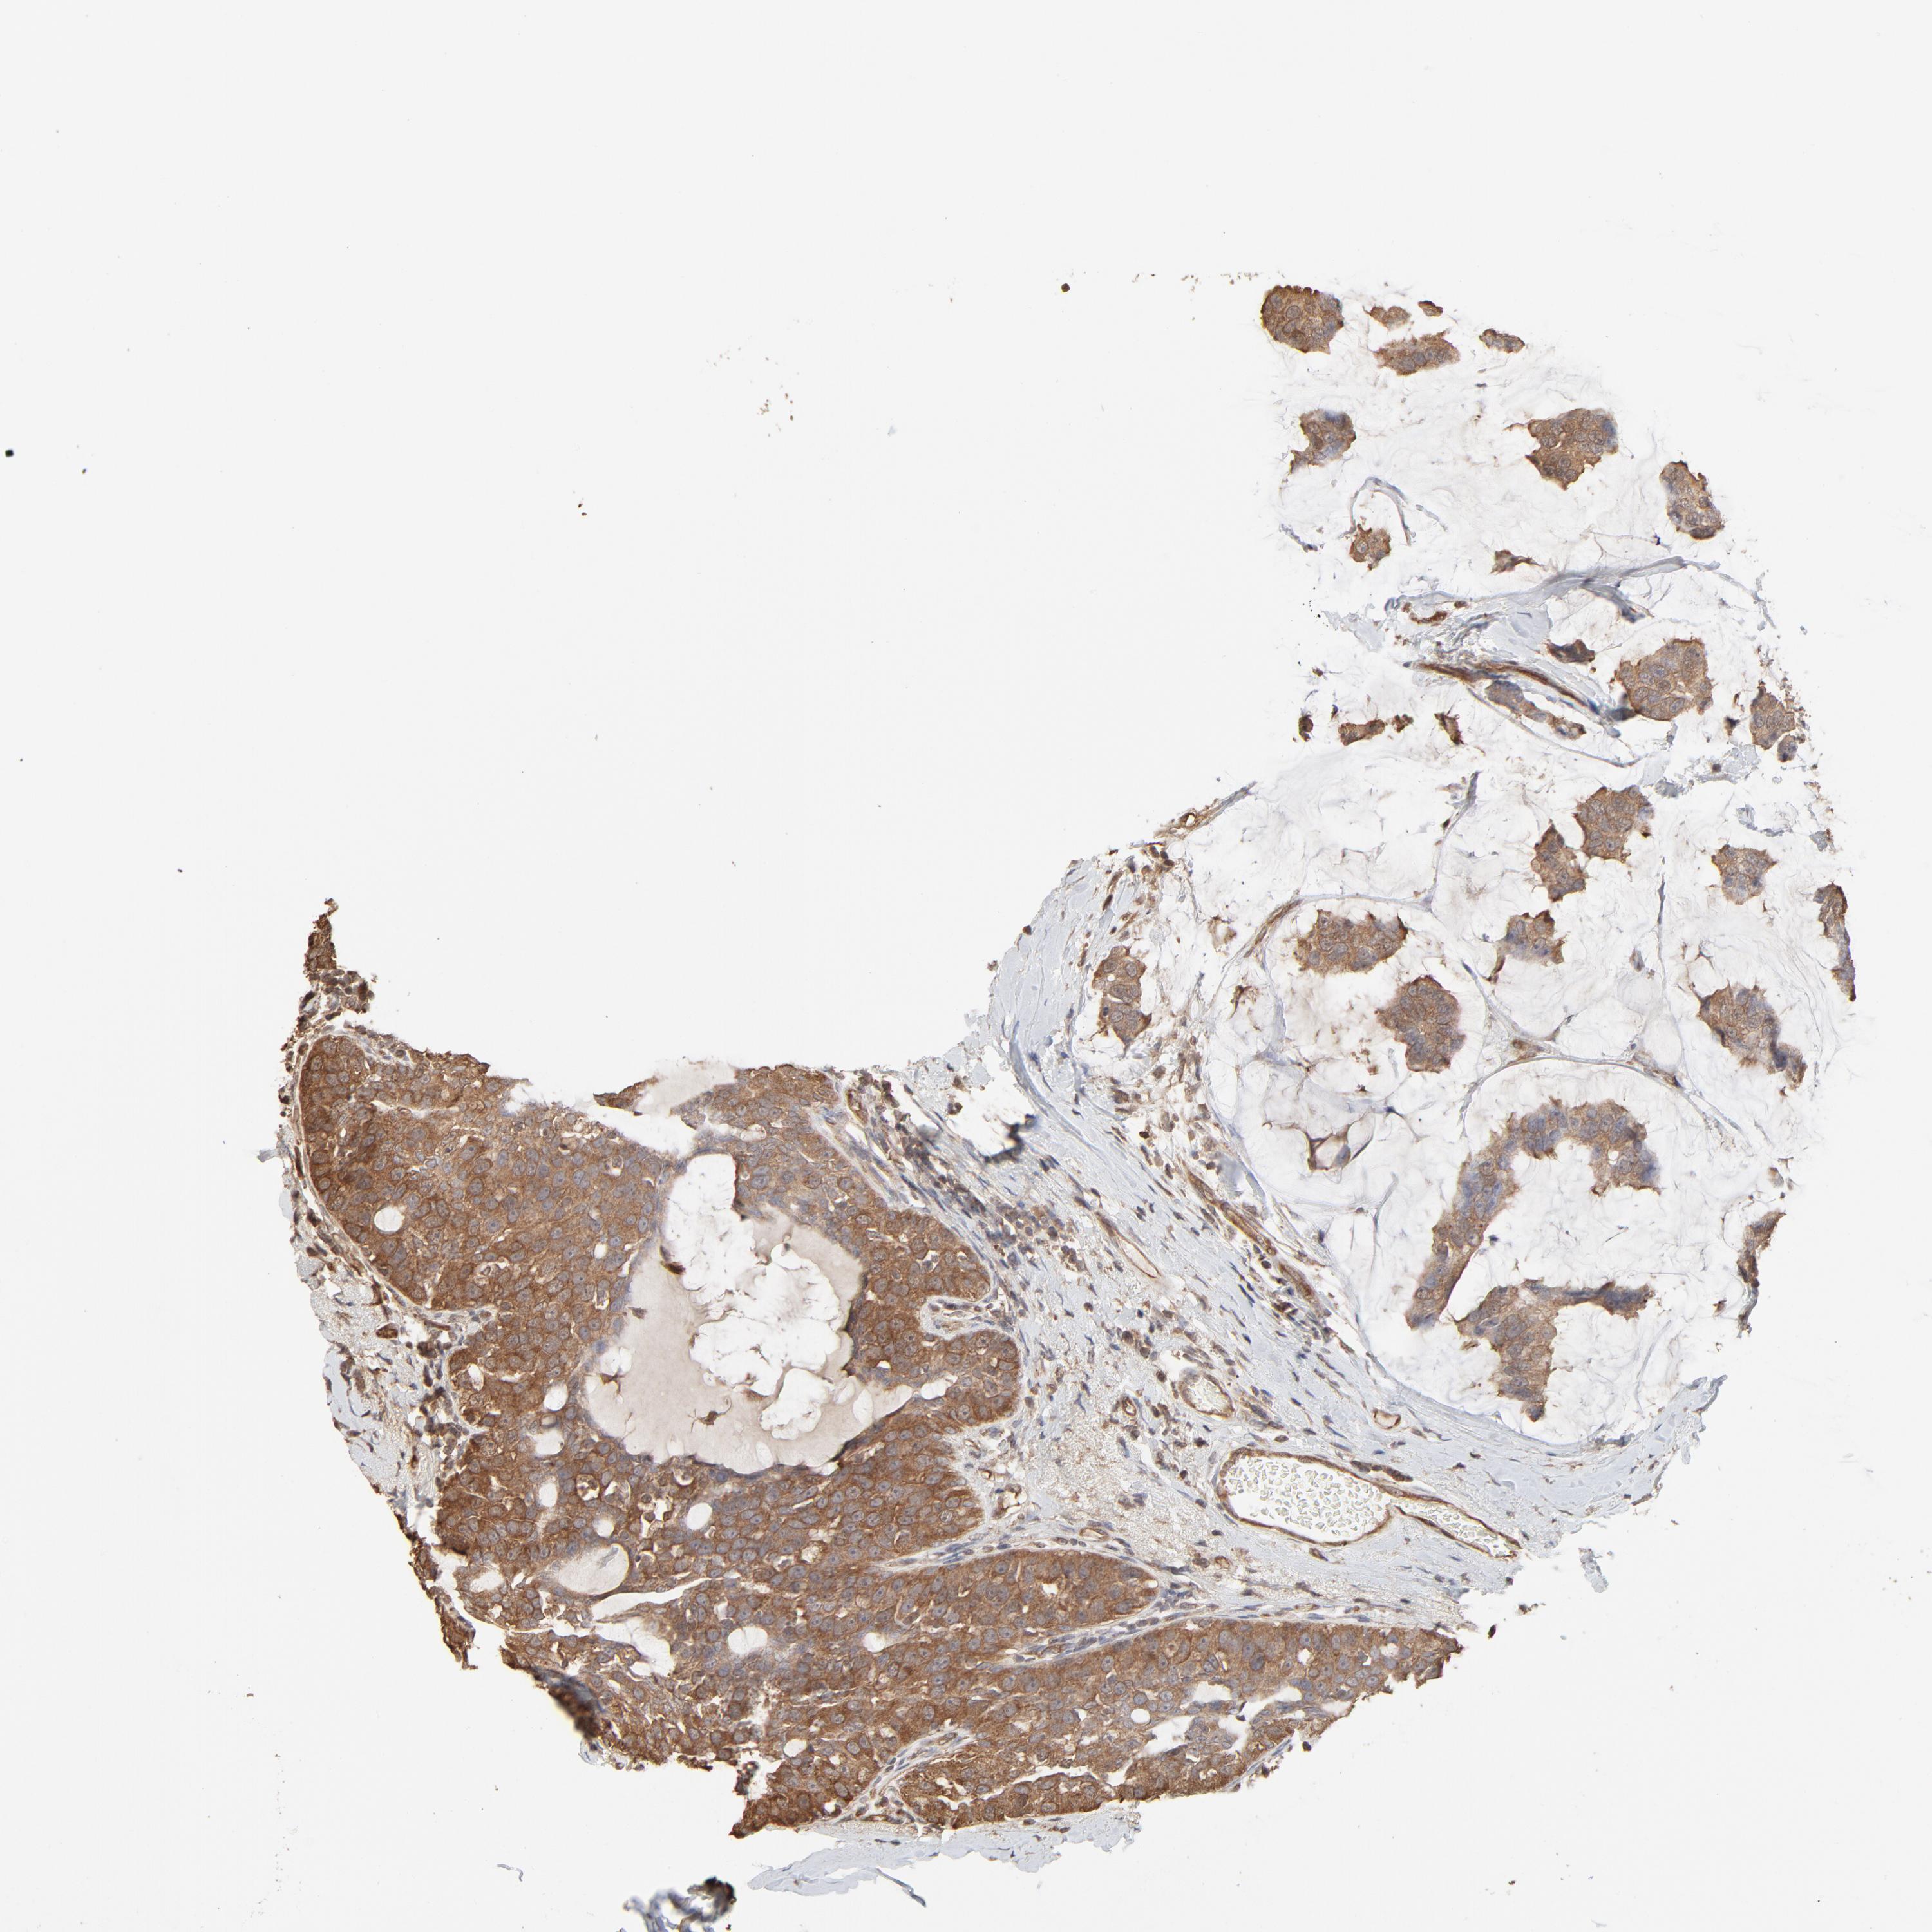

CANCER BREAST CANCER Show tissue menu

BRCA TCGA BRCA VALIDATION PROTEIN EXPRESSION

Breast cancer

Human cancer